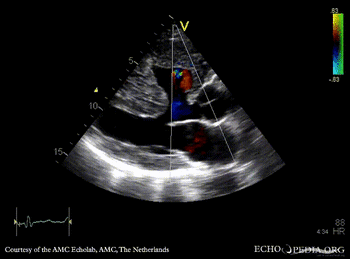

Large VSD, syndrome of Eisenmenger

A4CH

A4CH: Color Doppler